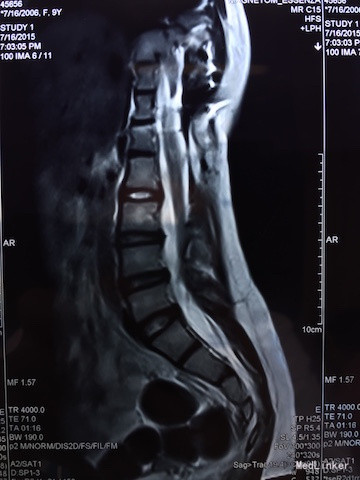

查体:四肢感觉、肌力及肌张力无明显异常,直腿高抬试验(-),双侧足背动脉搏动良好,腰椎活动可,病理征(-)。 辅助检查:胸腰椎MRI(如下图):脊髓下段受牵拉平对第3腰椎下缘,合并脊柱旁占位及脊柱裂可能。

诊断:脊髓栓系综合征 治疗:脊髓栓系松解术

随访与讨论:手术顺利,术后神经受牵拉症状需至少半年才能恢复。诊断及鉴别诊断:脊髓栓系综合征:是由多种脊髓先天性发育异常导致的系列临床综合征。脊髓下段因各种原因受制于椎管终末端,使其位置低于正常。根据该患者临床表现及影像学检查,考虑可能性大。马尾综合征:大多是由于各种先天性或后性原因之腰椎管绝对或相对狭窄,压迫马尾神经而产生一系列神经功能障碍,可有会阴区感染异常及大小便失禁,根据该患者影像学检查。